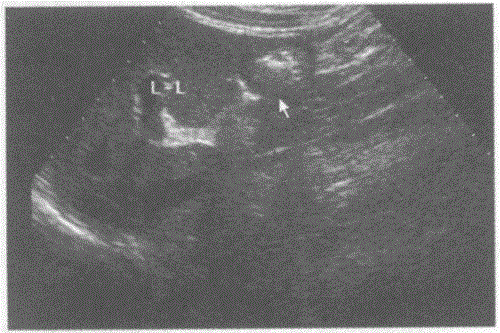

请回答下图是采用哪种肝脏扫查方式:A.肝一胃纵切声像图B.肝一下腔静脉纵切声像图C.肝一腹主动脉纵切声像图D.肝胆囊纵切声像图

选项 A.肝一胃纵切声像图 B.肝一下腔静脉纵切声像图 C.肝一腹主动脉纵切声像图 D.肝胆囊纵切声像图

答案 A